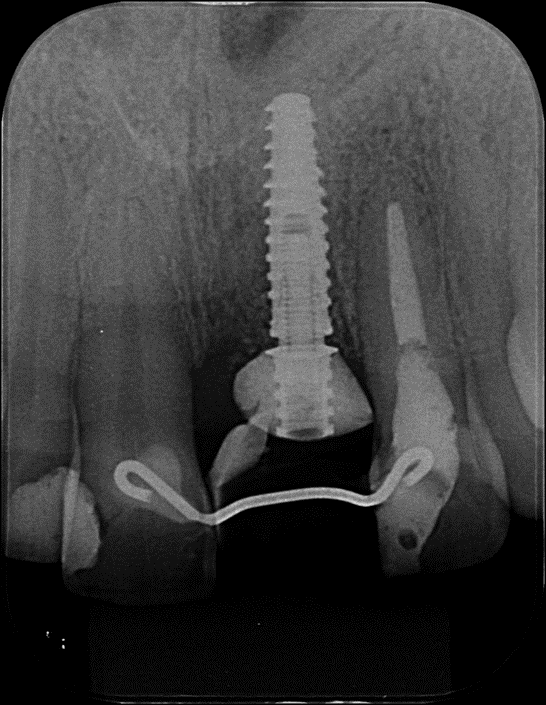

Radiografia Periapical inicial para auxilio no diagnóstico.

Após exame clinico e tomográfico, foi observado comprometimento periodontal e trinca radicular no dente 21.

Rádiografia Periapical final.